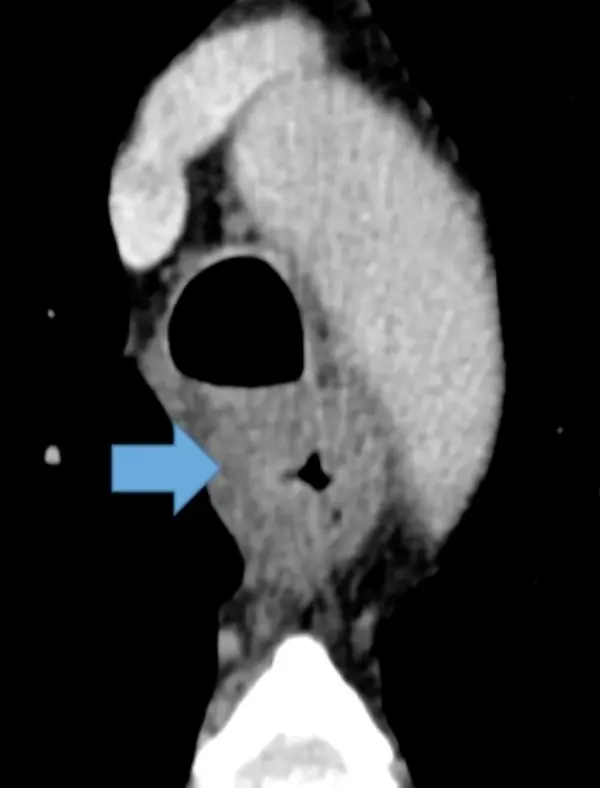

Example: 75 y/o with asymmetric thickening of esophagus prompting endoscopy â Dx: Carcinoma.

Example: 67 year old male with diffuse symmetric thickening of esophagus â Dx: Carcinoma